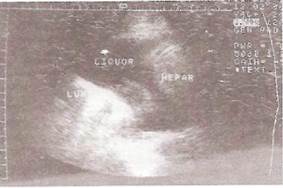

Ультразвуковое исследование

Ультразвуковое исследование легких позволяет обнаружить в плевральной полости даже малые количества свободной жидкости. При этом между обоими листками плевры, раздвигающимися при скоплении жидкости в полости плевры, обнаруживают однородное эхонегативное пространство, толщина которого зависит от объема плеврального выпота. Ультразвуковое исследование используют обычно для нахождения оптимального места для пункции плевральной полости и контроля за проведением торакоцентеза.

Массивный выпот (диффузный плеврит)

Плеврит, выявленный только при УЗИ

Осумкованный плеврит.